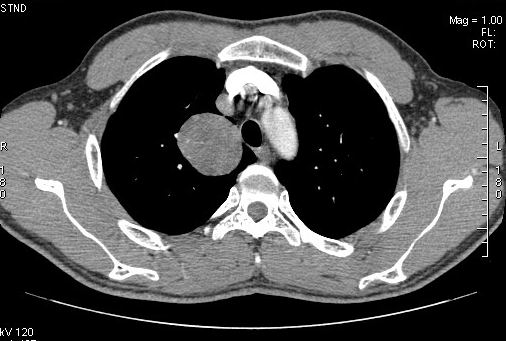

标题: CT7610:[原创]右上纵隔还是肺内占位,请会诊!

体检发现,无任何不适。

右肺见纵隔旁见类圆形界清等密度肿块影,直径约5.0cm,增强呈不均匀强化,重建的图片上看到肿块内可见强化的血管影,考虑:1,肺腺瘤;2,肺肉瘤。